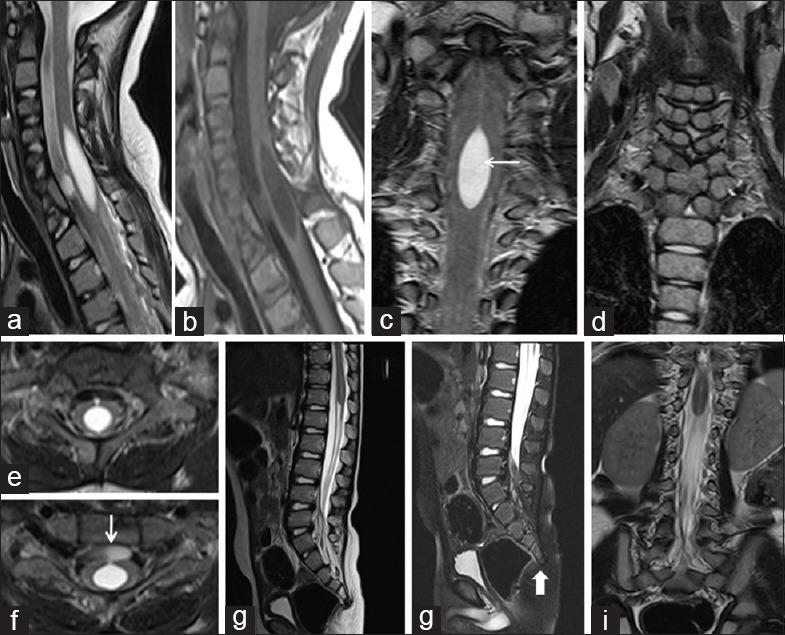

In our study, 21 pediatric patients were diagnosed with sacral agenesis/dysgenesis related to CRS. According to the Pang's classification, 2 (9.5%) patients were Type I, 5 (23.8%) patients were Type III, 7 (33.3%) patients were Type IV, and 7 (33.3%) patients were of Type V CRS. Clinically, 17 (81%) patients presented with urinary incontinence, 6 (28.6%) with fecal incontinence, 9 patients (42.9%) had poor gluteal musculatures and shallow intergluteal cleft, 7 (33.3%) patients had associated subcutaneous mass over spine, and 6 (28.6%) patients presented with distal leg muscle atrophy. MRI showed wedge-shaped conus termination in 5 (23.8%) patients and bulbous conus termination in 3 (14.3%) patients above the L1 vertebral level falling into Group 1 CRS while 7 (33.3%) patients had tethered cord and 6 (28.6%) patients had stretched conus falling into Group 2 CRS.

在我们的研究中,21例小儿患者被诊断为与CRS相关的骶骨发育不全/发育异常。根据庞氏分类,2例(9.5%)患者为I型,5例(23.8%)患者为III型,7例(33.3%)患者为IV型,7例(33.3%)患者为V型CRS。临床上,17例(81%)患者出现尿失禁,6例(28.6%)出现大便失禁,9例(42.9%)患者臀肌发育不良且臀间裂浅,7例(33.3%)患者脊柱上方有皮下肿块,6例(28.6%)患者出现小腿远端肌肉萎缩。MRI显示,5例(23.8%)患者在L1椎体水平以上出现楔形圆锥终丝,3例(14.3%)患者出现球茎状圆锥终丝,属于1组CRS;7例(33.3%)患者有脊髓栓系,6例(28.6%)患者有圆锥拉长,属于2组CRS。